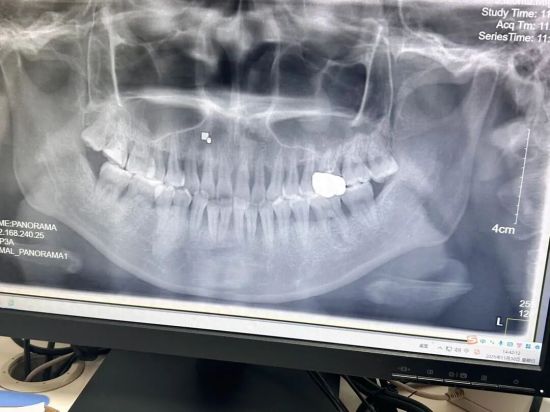

赵玥今年27岁,她的牙周病史则能追溯到大学时期。当时,她突然发现刷牙时牙龈会出血,但对牙周病了解甚少,只是简单去医院定期洗牙。赵玥所在城市不发达,医生未提及牙周病问题,加之洗牙后出血的症状确实减轻了,以为算是好转,但其实病程并未中断。去年在武汉就医时,她已有一颗牙酸痛、轻微晃动,被确诊为重度牙周病,测量出牙周袋深度达7—10毫米。

2025年11月,赵玥于武汉市一家三甲牙齿专科医院拍摄的牙片 图/受访者提供

牙周病分为牙龈病和牙周炎两类。首都医科大学附属北京同仁医院口腔科主任林江向《中国新闻周刊》介绍,牙龈病主要局限于牙龈软组织,大部分情况下可逆转,而牙周炎涉及牙周骨头的深度病变。“骨头一旦吸收掉,就不可逆了。”牙周病病程可漫长至十几年,许多牙周病患者来医院拍口腔CT时,用于支持牙齿稳定的牙槽骨都吸收了一大半,牙齿明显晃动,却仍坚称“没有感觉,还能吃饭”。